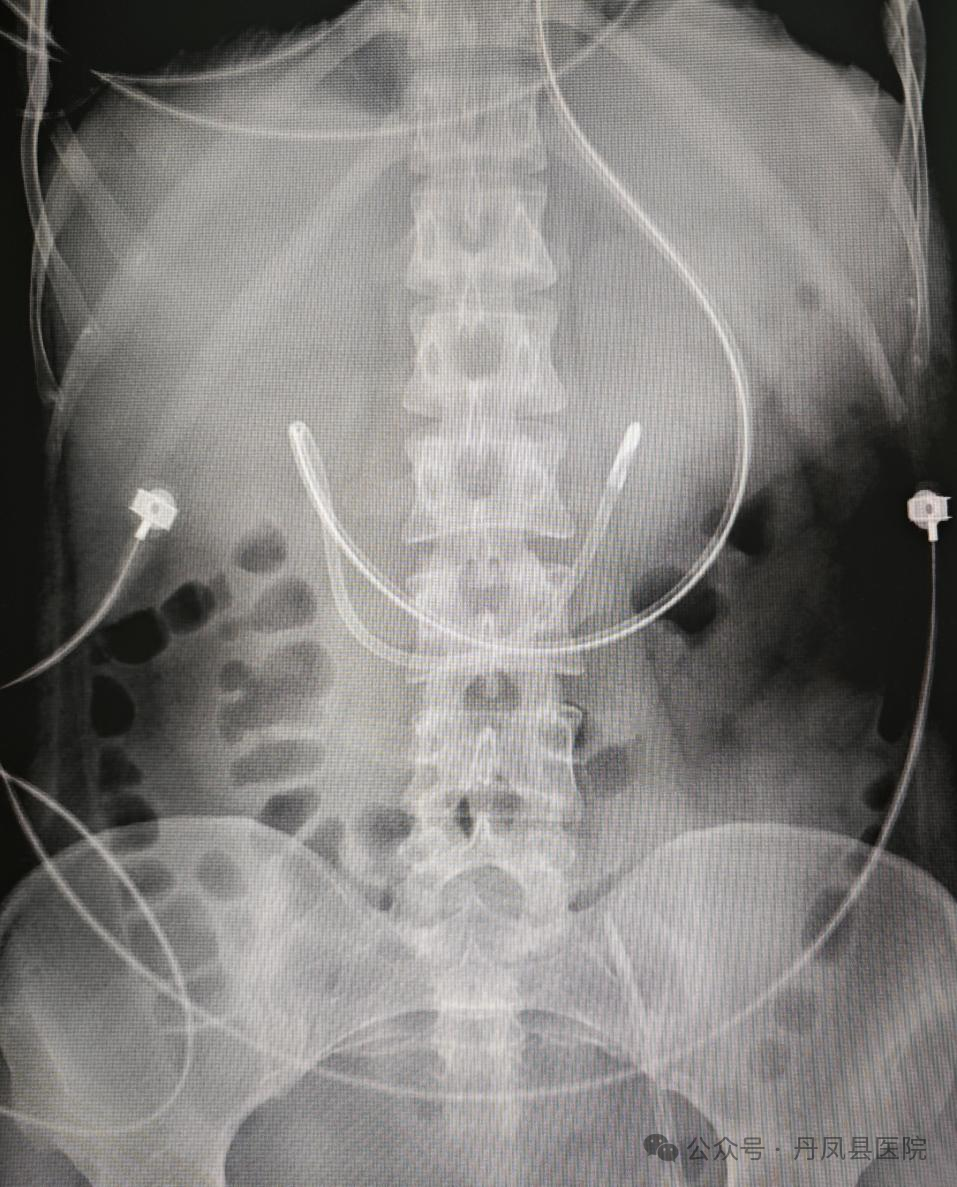

该患者为一名女性患者,一周前因车祸受伤,急行颅脑CT示:急性特重型闭合性颅脑损伤,于7月11日转入重症医学科,入科时患者经鼻胃管进食,出现了反流的情况,为避免加重肺部感染,经医生组商讨需要实施空肠营养支持治疗。接到医嘱后,在重症医学科护士长董萍的精准操作下,为患者在床旁顺利完成插管,术后腹部X线检查显示导管在位。

置管后腹部平片显示置入成功位置良好“鼻胃管就是从鼻子插入一根细管到胃里,通过这根管子把营养液和药物输送到胃里。而空肠管也是从鼻子插入一根细管,但要比胃管更长、更深、更细,这根管子通过幽门到达患者的十二指肠或空肠,能有效防止食物及胃内容物反流,降低误吸的发生率,减少吸入性肺炎的发生,也能更好地保证肠内营养进行,增加患者对肠内营养的耐受性。”董萍护士长介绍说。